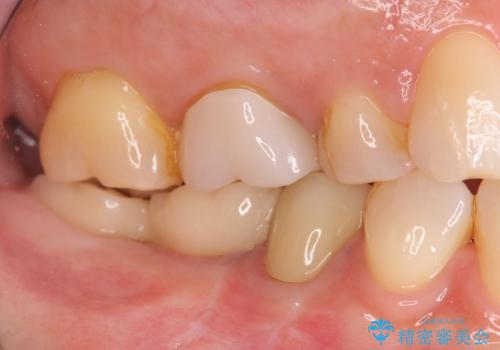

インプラント治療を行うにあたり周囲に骨を造成することで安定して噛める環境の整備を計画します。

今回はインプラント埋入時に固定が得られたので同時に骨の造成を行い治療を進めることができました。